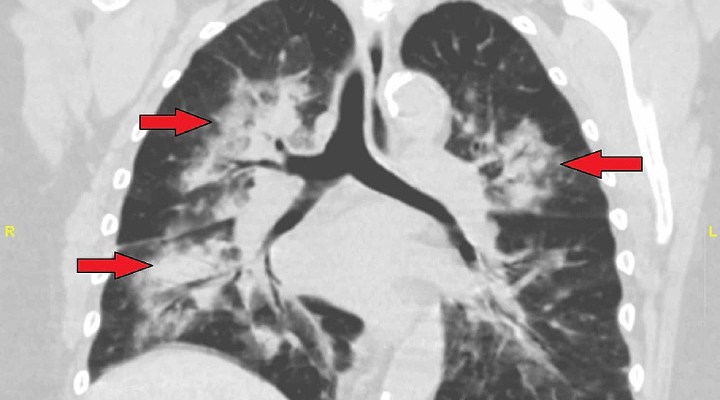

تشخیص خلط خونی از روی عکس قفسه سینه

به گمان زیاد پزشک درمورد داروها، بیماری قبلی یا سیگاری‌بودن شما سوال بپرسد. سپس پزشک علائم بیماری‌های مربوط به سرفه خونی را بازدید می‌کند. این چنین دمای بدن شما را برای بازدید عفونت می‌گیرد و بینی شما را بازدید می‌کند تا یقین بشود خون‌ریزی از بینی نیست. با دقت به شرایط، به گمان زیاد به عکس‌برداری پرتوی ایکس از قفسه سینه یا سی.تی اسکن نیاز دارید تا هر مشکلی تشخیص داده بشود. این چنین امکان پذیر به برونکوسکوپی نیاز داشته باشید. برونکوسکوپی روشی است که با آن درون مجاری هوایی و ریه دیده می‌بشود. اگر پزشک به وجود لخته خون در ریه شک کرده باشد، احتمالا اسکن تهویه-پرفیوژن ریه تجویز کند تا جریان هوا و جریان خون در ریه بازدید بشود.